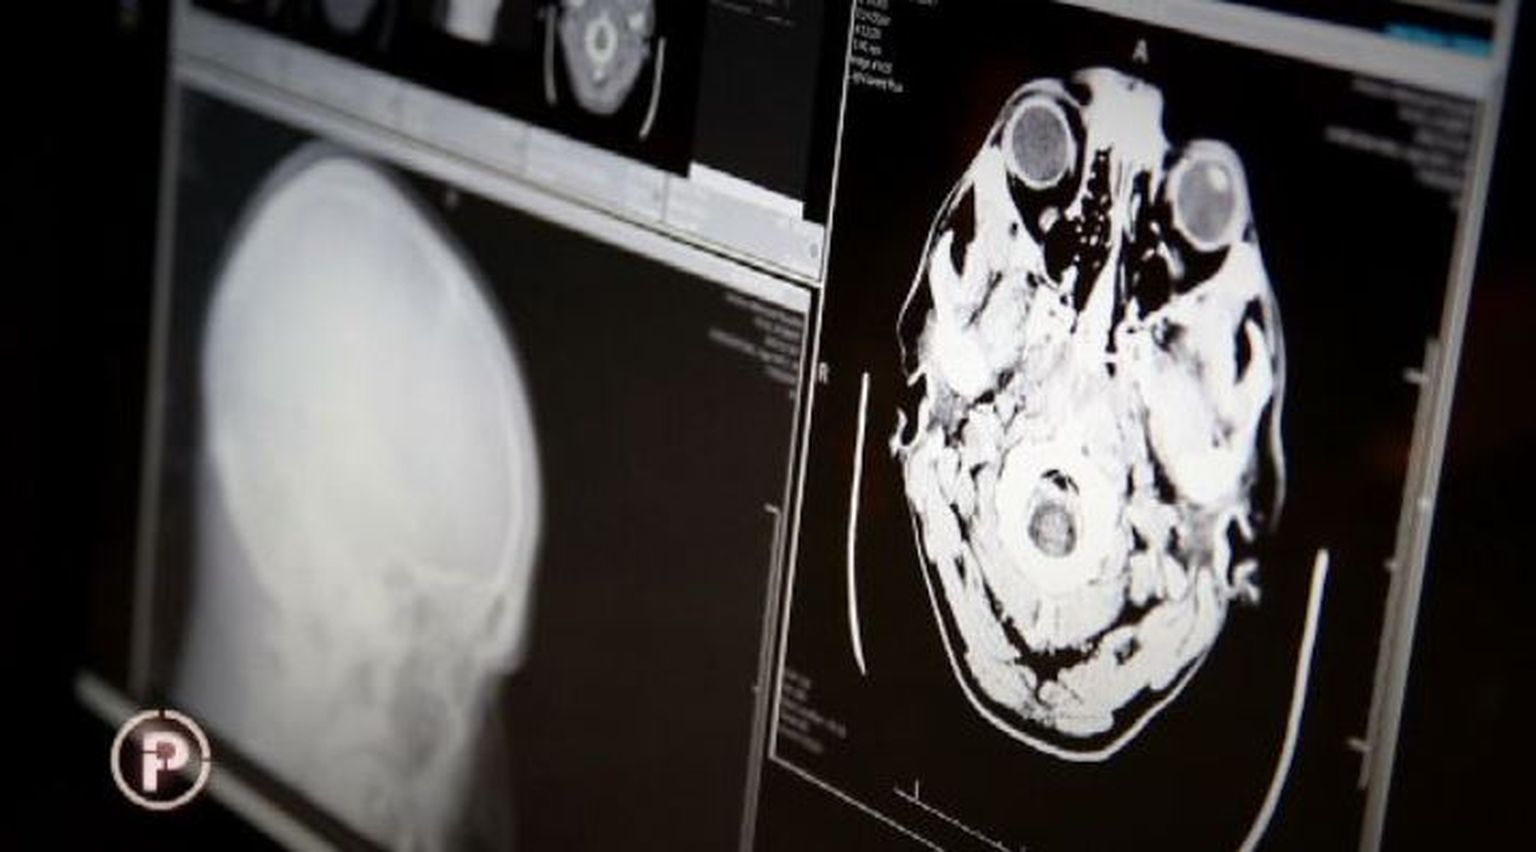

• Rendgenska snimka ozljede glave Foto: Provjereno